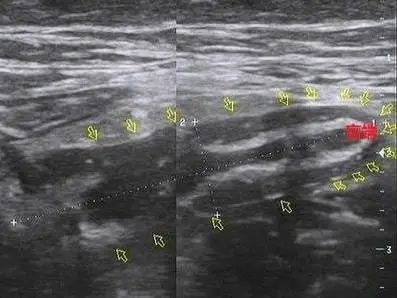

通过问诊、查体以及化验、彩超、腹部CT等辅助手段排除相关疾病并确认阑尾炎。因为彩超快速便捷、价格低、可多次复查随访等优点,可作为首选检查。

若彩超发现阑尾肿大是患阑尾炎的直接证据;若当时检查未发现阑尾,但是右下腹淋巴结较多、腹腔积液、腹痛明显、发热、血象高等都是患阑尾炎的间接证据,要高度怀疑阑尾炎,密切随访,不能漏过。